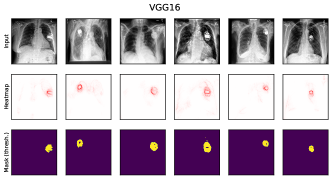

where denotes element-wise multiplication. This yields a heatmap that can be used as a soft mask or converted to a binary segmentation mask, for instance using thresholding techniques like Otsu’s method [57]. An example is shown in Fig. 2 (right), showing soft masks as heatmaps from concept-conditioned local attribution scores, along with binary masks for three known data artifacts: rulers and band-aids for skin cancer detection, and pacemakers in chest radiographs.

6.4 Spatial Bias Localization

To spatially localize biases in input space with CAVs, we compute local explanations for the element-wise product of latent activations and concept direction (see Eq. 2). We use the controlled artifacts, specifically timestamp (HyperKvasir) and micropscope (ISIC2019) with ground truth concept localization masks for evaluation. We compute (1) the percentage of relevance within the ground truth mask and (2) the Jaccard index, or Intersection over Union (IoU), of the binarized localization mask with the ground truth. In Fig. 9, we report both metrics using CAVs computed on different layers of VGG16 and ResNet50. The layer choice for concept representations is key, as for example middle layers perform better to localize timestamps and earlier layers are more effective to localize the microscope. In comparison with Fig.7, we find that the optimal layer for bias localization may differ from the one for sample retrieval. Interestingly, the IoU for the microscope artifact is consistently low, as models primarily focus on the border of the circle instead of the entire area, as indicated by qualitative results in Appendix A.6.3. Unlike artifact relevance, the IoU metric also measures how much of the expected areas the computed mask does not cover.